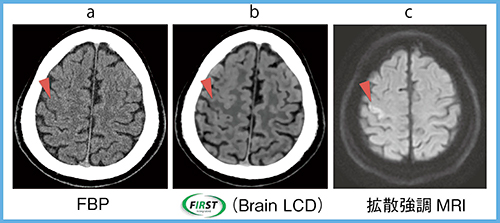

3.線質硬化現象の補正

FIRSTのビームハードニングモデルでは,生データ上で三次元の高精度な線質硬化補正を行うことで,従来よりも正確な補正が可能である。高吸収な骨に囲まれた頭部でも,線質硬化現象によるアーチファクトを除去し,かつ高コントラストでノイズの少ない明瞭な画像を得ることができる。

急性期脳梗塞の症例では,FBP(図6 a)ではノイズが多くコントラストが低いため梗塞巣を認識することは難しいが,FIRST(Brain LCD)(図6 b)ではMRIの拡散強調画像(図6 c)の梗塞巣に一致して灰白質,白質のコントラスト低下が明瞭に認められる。

図6 頭部CT(急性期脳梗塞)